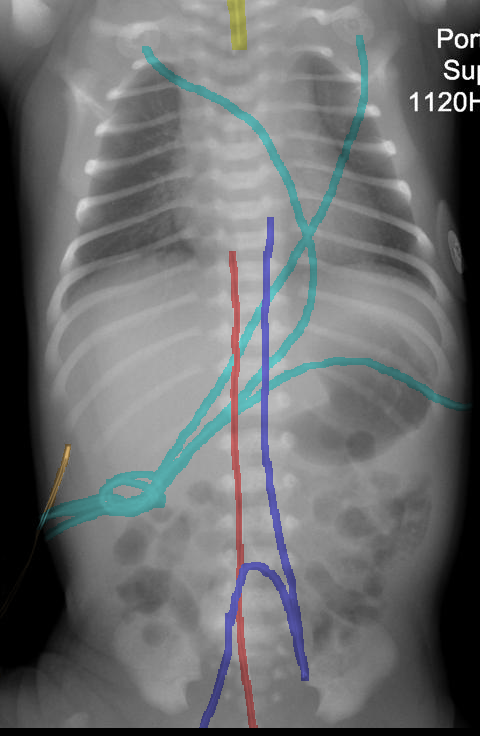

Automated catheter detection is a challenging task. Although most catheters have a radiopaque strip to facilitate detection, the strip may become less apparent depending on the projection angle. Catheters maybe confused by other similar linear structures like ECG leads and anatomy including ribs. Additionally, portions of catheters can be occluded by anatomical structures given that radiographs are a 2D projection of a 3D structure. For example, when a NGT is placed within the oesophagus, the catheter itself becomes less apparent due to the high density of the adjacent vertebrae. Finally, the number and type of catheters that could possibly appear in pediatric X-rays are unknown a priori. The catheters may be intertwined with each other thus making simple line tracing methods fail. Figure 1 gives three sample pediatric X-ray images with some common catheters highlighted in different colors.

To alleviate this annotation problem in catheter detection, we proposed to use X-ray images with simulated catheters by exploiting the fact that catheters are essentially tubular objects with various cross sectional profiles. To be more specific, a synthetic 2D projection of a catheter is generated by first simulating a horizontal catheter profile and then using it as a brush tip to draw along a B-spline path. This generated catheter is then composited with an X-ray image serving as the training data. Another contribution of this work is a segmentation network that can inherently take into account multi-scale information. This network adopts a UNet-style form and contains a recurrent module that can process inputs with increasing scales111Our code is available at https://github.com/xinario/catheter_detection.git.. We have empirically shown that by iterating through the scale space of the input image, higher recall is achieved as compared to using a single scale. Details about the methods are discussed in Section 3. Three sample detection results are shown in Figure 1.

The test dataset is collected locally and only contains frontal chest-abdominal X-rays from patients < 4 weeks old. This is the most common radiograph obtained to confirm placement of catheters such as UACs and UVCs in neonates. Currently, the test set has 35 fully labeled images with different catheter types with sample images previously shown in Figure 1. All the annotated catheters (lines excluding ECG leads) are treated as the same class in the detection.